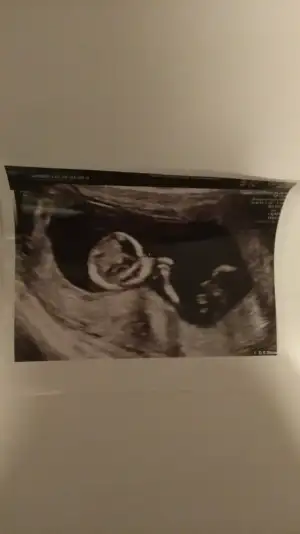

Net değil 12 13 haftada paylaşın sanki eminde değilim erkek gibi gibi![]()

Dr +getirmiş sanki erkek gibi gibi siz 12 13 hafta usg de paylaşın emin olamadımMerhabalar bizde burda 11 haftadaydik bizede tahmin edebilirmisiniz rica etsem ❤

Dr +getirmiş sanki erkek gibi gibi siz 12 13 hafta usg de paylaşın emin olamadım

Erkek gibiBuda diğer pozu o gün ki ölçüm olmayan ters duruyordu bunda ondan çevirip çektim resmini bunda da belli olmazsa 12 gün sonra kontrolümüz var o zaman atarım 14 haftalık olacak kısmetse o zaman ❤Ikra meyra cvp için teşekkür ederim ❤ diğer konuya da 6 haftalık halini atmıştım ama görmemiş tiniz sizin tahminleriniz genel olarak tutuyor ❤

Evet inşallah yaşayan ilk olcakErkek gibiteşekkur ederim evet cogunluk tutuyor bazı usg lerde yanıltıyor bazen pozisyonları nubu değiştiriyor vs ilk bebekmi